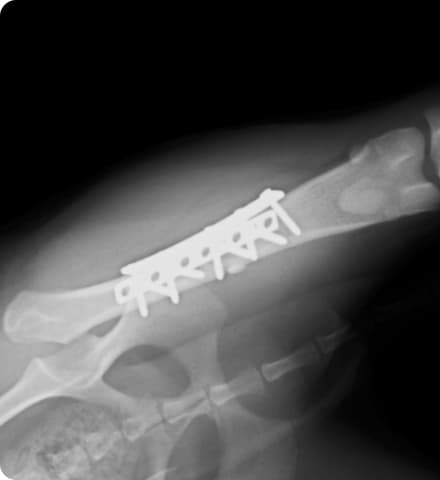

Orthopedic surgery

当院では骨折や靭帯断裂に対して、外科手術での治療を行っています。